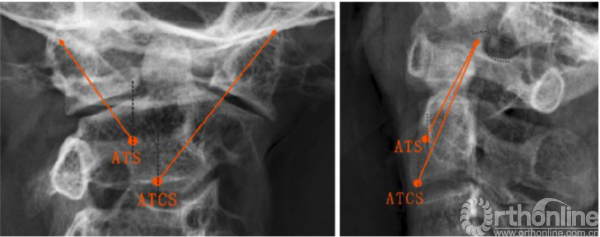

ATS和ATCS固定的轨迹可通过正、侧位X线片上的解剖标志来确定。在正位X线片中,螺钉轨迹朝向C1上关节突上外侧角,与侧块外侧缘间隙为2-3mm(图3,左)。然后测量α角,即ATS与ATSC螺钉相对于矢状面所形成的理想外展角。在侧位X线片中,ATS和ATCS固定方向均朝向C1上关节突后上角,并与上关节突后缘的间隙为2.3mm(图3,右)。此外,还测量了角β,即ATS与ATSC螺钉相对于冠状面所形成的理想倾斜角。将螺钉置入新鲜尸体标本后,在正、侧位X线片上分别测量ATS和ATCS的实际角α、β,以及ATCS和ATS的实际进钉点与C2椎体中线的横向距离。

图3正位和侧位x线片上ATS和ATCS的螺钉轨迹,(左)所有螺钉对准C1上关节突上外侧角;(右)所有螺钉对准C1上关节突上角(点附近);ATCS,前路经关节交叉螺钉;ATS,前路关节交叉螺钉

The ATS and ATCS trajectories were determined using the landmarks visible on anteroposterior and lateral x-rays. On the anteroposterior view, screw trajectories were aimed at the superolateral corner of C1 superior articular process, leaving 2–3 mm clearance from lateral margin of the lateral mass (Fig. 3, left). Then, the angle α, the ideal lateral angle of ATS and ATCS placement relative to the sagittal plane were measured. On the lateral view, the trajectories of ATS and ATCS were aimed at a point on the line between the superoposterior corner of C1 superior articular process and the superior end of the anterior arch, with 2–3 mm clearance from posterior margin of the superior articular process (Fig. 3, right). Moreover, the angle b, the ideal incline angle of the two screws placement relative to coronal plane were measured. After the screws were inserted into fresh cadaveric specimens, the actual angle a and b of ATS and ATCS were also measured on anteroposterior and lateral X-ray images, respectively, as well as the actual entry points of ATCS and ATS lateral from the midline of the C2 vertebrae.

Fig. 3 Trajectories of ATS and ATCS are shown on anteroposterior (left) and lateral radiographs (right). (left) All screws are aimed at the superolateral corner of C1 superior articular process; (right) All screws are aimed at the superoposterior corner of C1 superior articular process (around dot). ATCS anterior transarticular crossing screw, ATS anterior transarticular screw